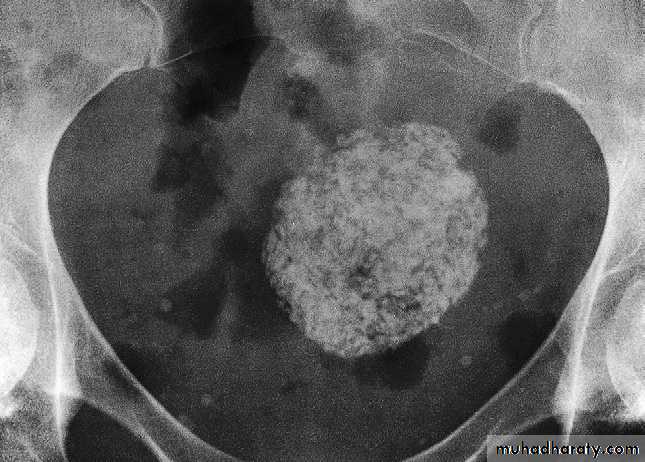

A dermoid cyst can usually be confidently diagnosed because of the fat within it, and it may contain various calcified components, of which teeth are the commonest.

These ovarian tumours are predominantly benign and can usually be recognized on ultrasound but are also readily diagnosed on CT or MRI and sometimes on plain radiographs .

FibroidsLeiomyomas (fibroids) are common in women over 30 years of age. They are often asymptomatic, but may cause menorrhagia or present as a palpable mass. When sufficiently large, a fibroid can be seen on a plain film as amass in the pelvis and may show multiple irregular but well-defined calcifications .